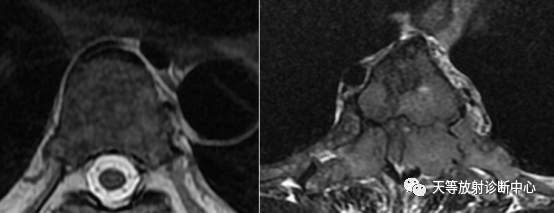

▲ T2 混杂高信号及多发性线样低信号,其骨皮质增厚及辐射形式与脑实质形态相似,称之为“迷你脑”征。文献报道该征可以特异诊断浆细胞瘤。